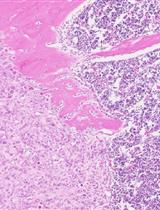

Even though the survival and proliferation stages of cancer cells that have newly settled at a metastatic site are the rate-limiting stages and the most promising targets for drugs, there is a lack of models of the earliest stage of metastasis formation. A method for modeling breast cancer liver metastasis is described here: a stage of transition of a differentiated tumor cell into a cell actively proliferating in a three-dimensional (3D) liver spheroid. Opposite to existing heterocellular 3D models of metastases, the protocol allows modeling the initial stage of liver colonization by metastatic cells, the so-called “micrometastases.” The method includes obtaining a line of fluorescent tumor cells, fluorescence-activated sorting of differentiated cells, preparing a single-cell suspension of liver cells, forming a liver spheroid in an agarose mold, inducing the tumor cell dedifferentiation and proliferation using IL-6, and intravital microscopy of spheroids, with subsequent processing and analysis of fluorescent images in the ImageJ software. The performance of the proposed model was demonstrated using microRNA therapeutics. The ability of a combination of microRNAs to suppress the transition of micrometastasis to macrometastasis in the 3D liver spheroid was confirmed by an immunofluorescent assay of spheroid sections and transcriptome analysis.

Validation of the proposed model was performed using miRNA therapeutics. Recently, we proposed a strategy for metastasis prevention with the help of a combination of three miRNAs that inhibit stemness genes, block the dedifferentiation of cancer cells in a metastatic niche, and prevent macrometastasis formation. In the original work, to confirm the efficacy of the combination of miRNAs, via intravenous administration of miRNAs in liposomal form, we conducted a series of experiments indicating the suppression of stemness gene expression, inhibition of mammosphere formation in vitro, and the prevention of metastasis in mice carrying experimental tumors [9]. In the present article, we confirm the ability of the combination of miRNAs to suppress the transition of micrometastasis to macrometastasis in our proposed model of breast cancer metastasis in a 3D liver organoid.